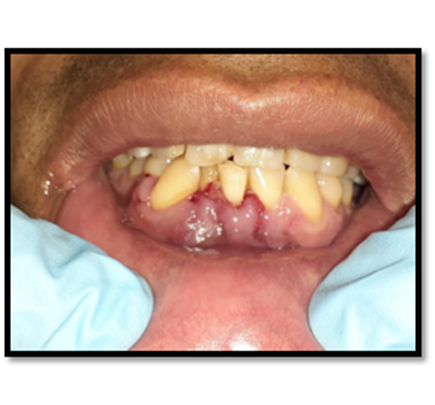

Imagen 13. Control posoperatorio.

Fue trasladado al área de

recuperación, para vigilar los signos vitales del paciente.

Imagen 14. Control posoperatorio.